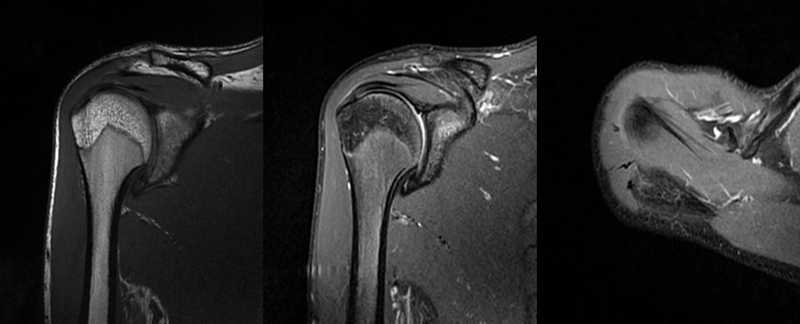

2、MRI检查

MRI目前是诊断肩袖疾病中最常用的检查,可以直观的观察肩袖肌腱。

图17 冈上肌

图18 冈下肌

图21 斜冠状位(临床常用)a.T2,b.T1

图22 斜矢状位 a.冈上肌出口,肩袖诊断不如斜冠状位;b.冈上肌及肌腹脂肪浸润成度,评估手术与否

图24 a.肩袖全层撕裂;b.正常MRI

图25 巨大肩袖损伤(冈上肌)